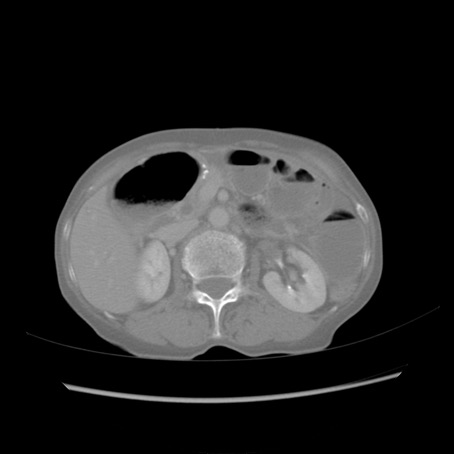

冠状断像

【症例】80歳代女性

【主訴】胸のつかえ感

【現病歴】約9時間前に食後から胸のつかえた感じあり、嘔吐あり、来院。

【既往歴】胃癌(全摘)、胆摘、虫垂炎

【身体所見】心窩部に圧痛あり、反跳痛なし。

【データ】WBC 5700、CRP 0.05